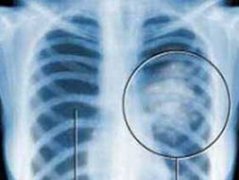

肺癌是现如今较为常见的恶性疾病在临床上,肺癌的转移现象中常见的就是骨转移,癌症的转移无疑是给患者二次打击,很多肺癌骨转移患者因为治疗不及时病情恶化更严重,那如何对肺癌骨转移进行治疗?让我们看看肺癌医生给出的答复。

对怀疑有骨转移的肺癌患者,应及时进行检查,骨转移瘤的主要症状为逐渐加重的局部疼痛,晚期可有病理性骨折,脊髓和神经压迫,甚至出现高钙血症。骨转移瘤所引起的疼痛等症状往往成为肿瘤患者的很大痛苦。椎体骨折可以引起脊柱变形、活动受限,甚至导致瘫痪。并发症的发生还可以对患者造成严重的心理影响,进一步严重降低癌症患者的生活质量。